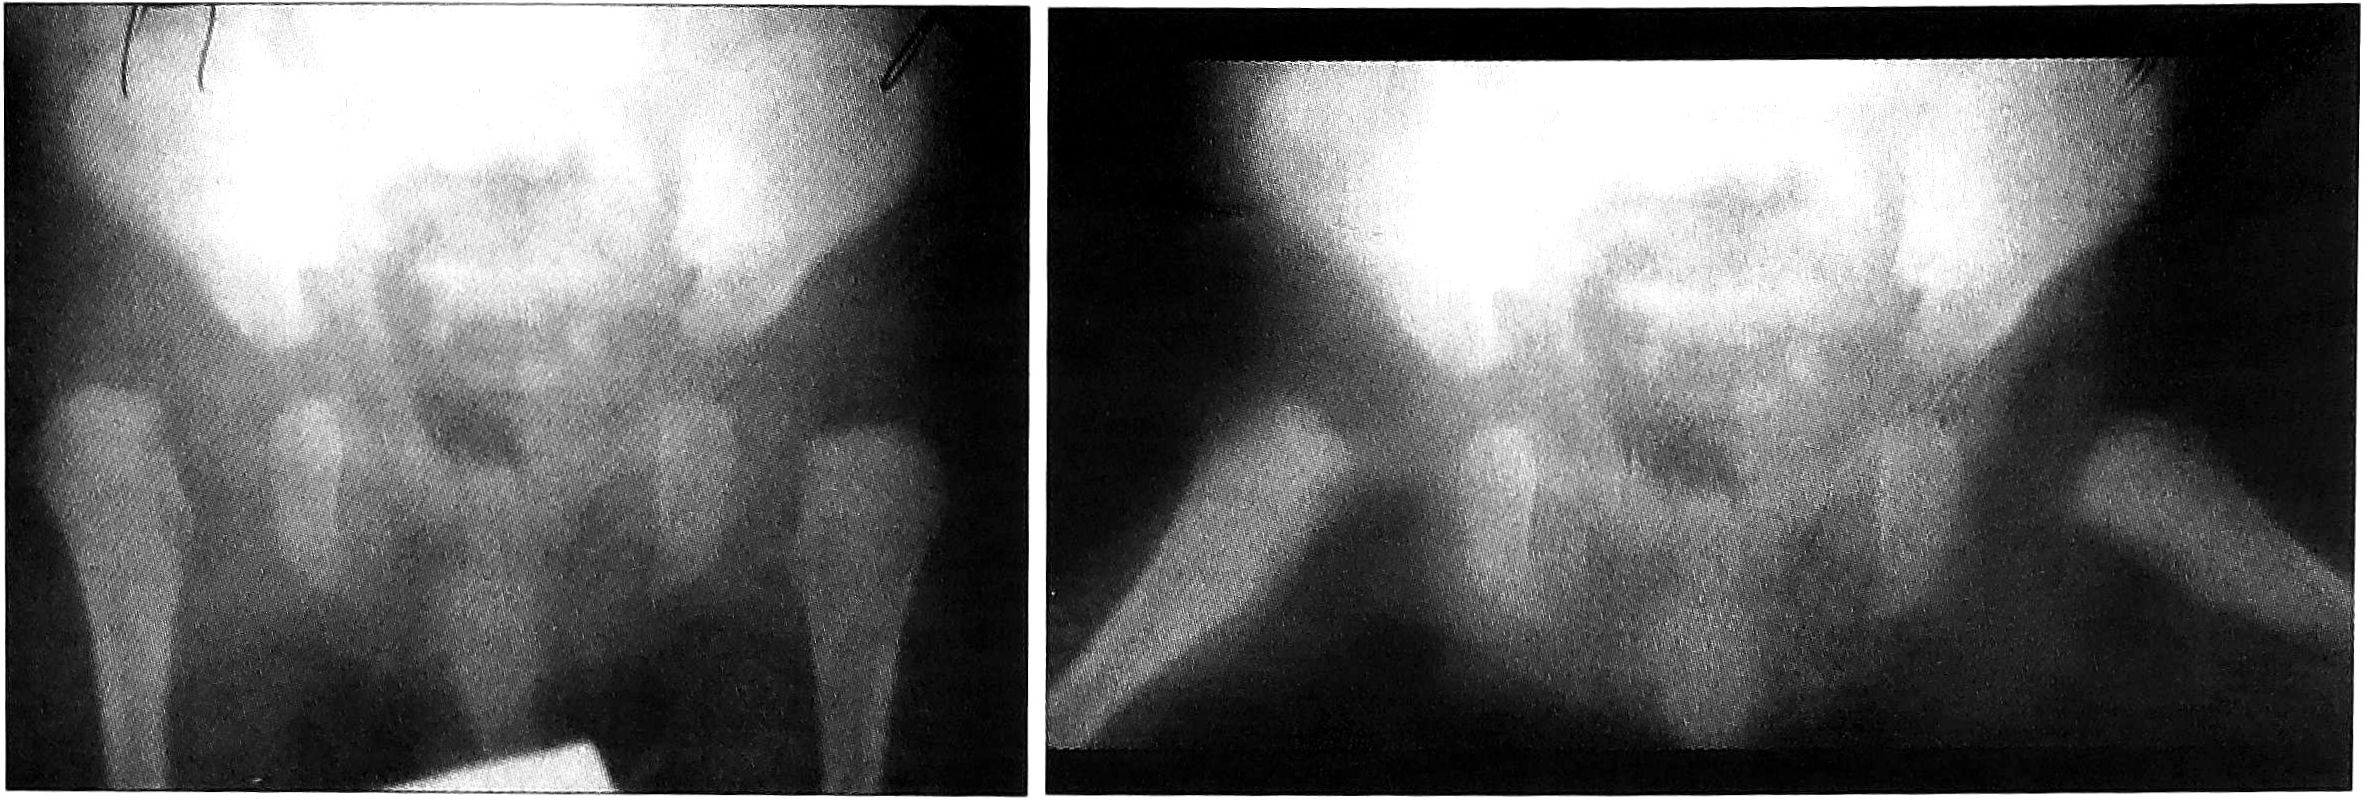

Закрытое вправление под наркозом проводилось 21 ребенку. В большинстве случаев предварительно накладывалось вытяжение в вертикальной или горизонтальной плоскости, последующая фиксация осуществлялась в кокситной гипсовой повязке. Некоторым пациентам вправление после вытяжения производилось без попытки применения щадящих функциональных методов. При обращении в ЦИТО после неудач закрытого вправления у больных на фоне не устраненного вывиха имелись различные осложнения лечения — контрактуры суставов, асептический некроз головки бедра, рубцы на коже после пролежней при длительной фиксации в гипсовой повязке (рис. 5).

Рис. 5. Осложнения после закрытого вправления головки бедренной кости. а — больная С. 2,5 лет, диагноз: врожденный вывих бедер. Состояние после неоднократного закрытого вправления. Асептический некроз головок обеих бедренных костей, сгибательно-отводящие контрактуры в тазобедренных суставах; в — рубцы в подколенной области у больной С. 2,5 лет после фиксации в бесподкладочной гипсовой повязке. б — больной Б. 3 лет, диагноз: врожденный вывих бедер. Состояние после неоднократных попыток вправления. Асептический некроз головки левого бедра, приводящая контрактура в левом тазобедренном суставе;